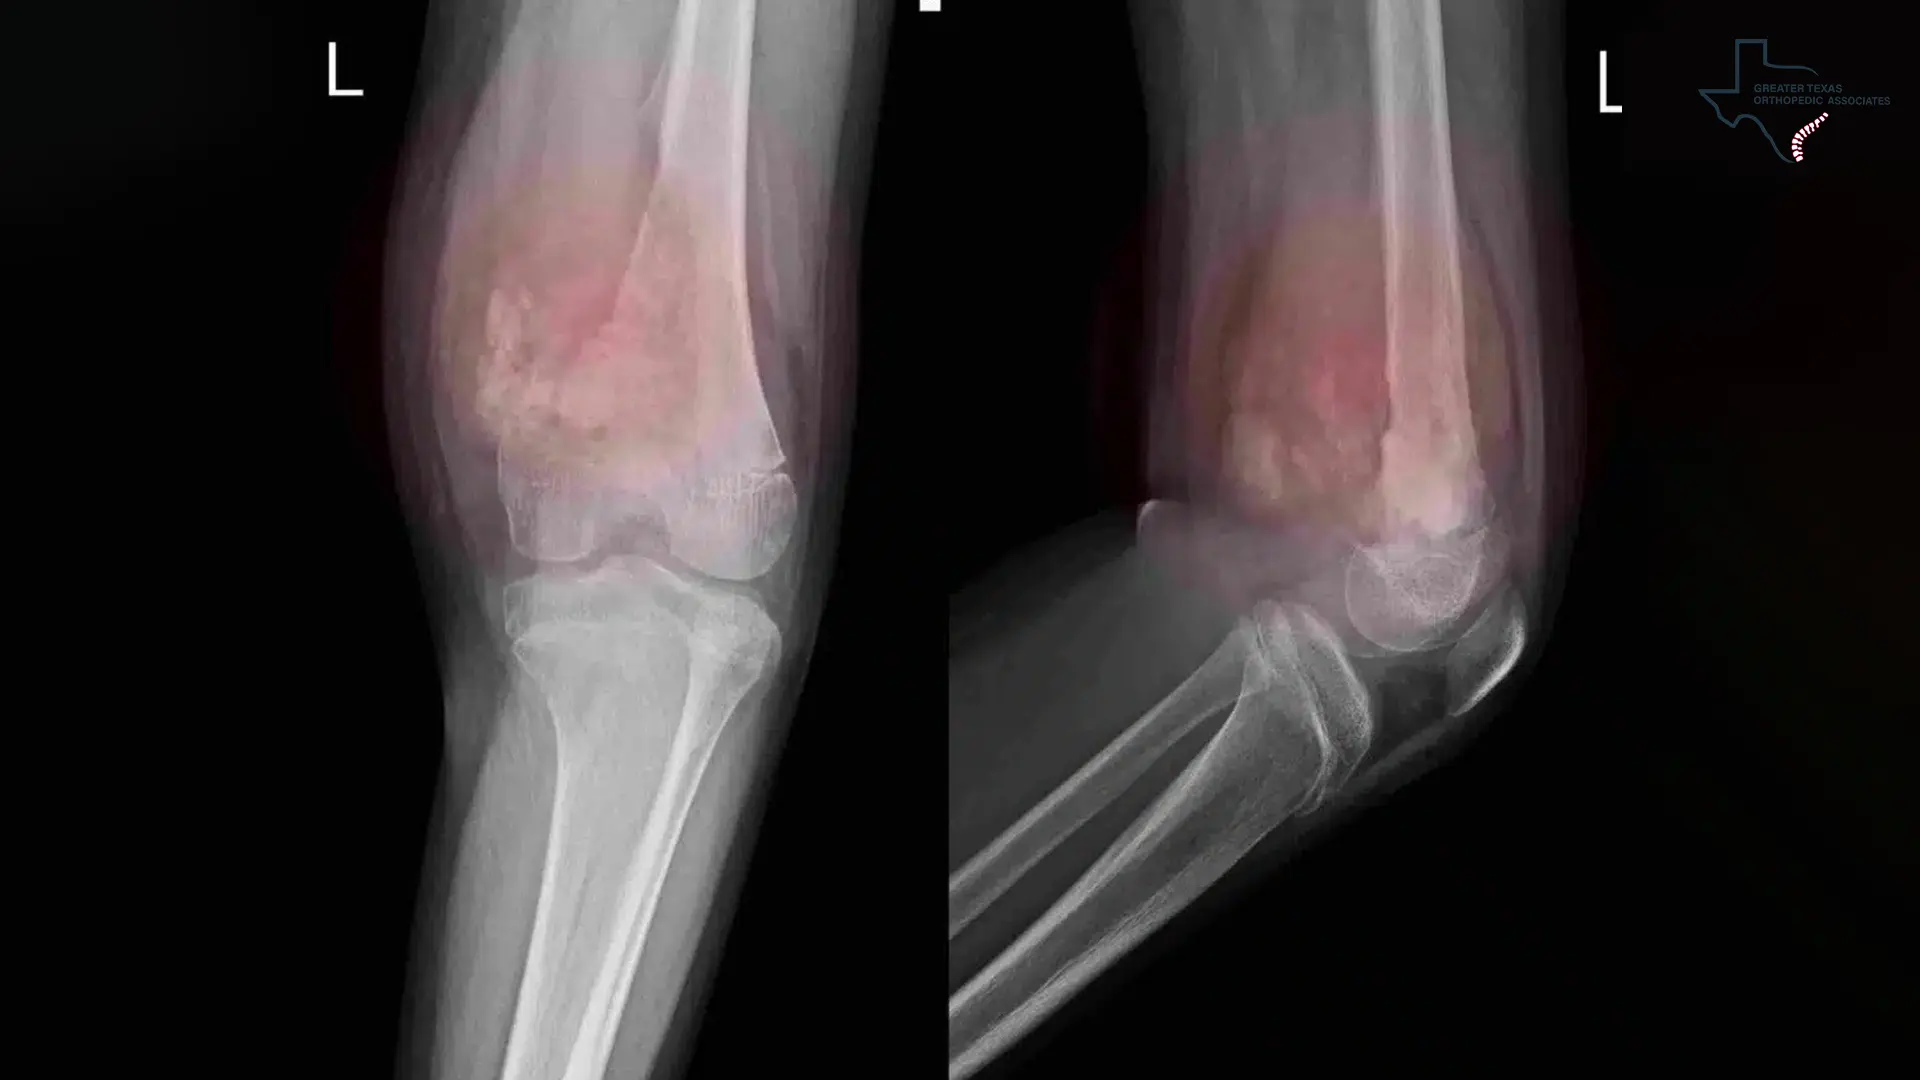

X-rays: These are quick, cost-effective, and widely available, excelling in visualizing skeletal abnormalities like fractures or dislocations. While limited in soft tissue assessment, X-rays are indispensable as a first-line screening tool to rule out bone-related injuries.

While soft tissue injuries are often invisible on basic X-rays, specific diagnostic imaging techniques provide the necessary Medical Proof for Soft Tissue Damage to validate the claim.